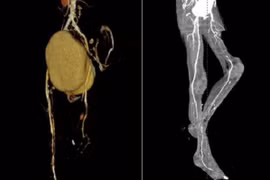

Một bác sĩ người Mỹ đã phát minh ra bài kiểm tra, chỉ cần động tác đơn giản là gập ngón tay cái lại... từ đó có thể biết được nguy cơ sưng, phình động mạch chủ.

Nhiều bệnh nhân bị liệt, hoại tử ngón chân hoặc phải cắt bỏ cả chi mới biết mình bị bệnh tắc động mạch chi chứ không phải đau xương khớp. Mùa đông lạnh, ẩm gây co thắt mạch máu khiến bệnh tắc động mạch chi gia tăng từ 10 – 15%.